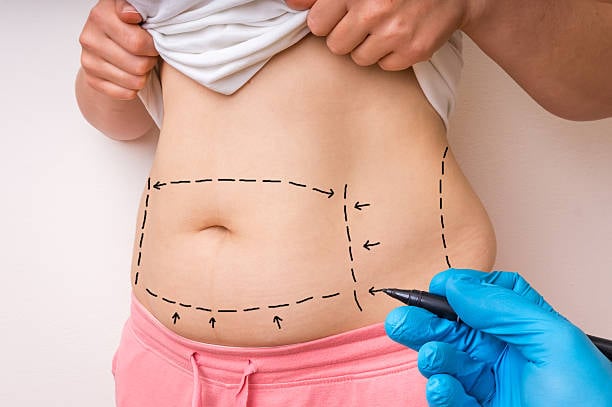

أصبح شفط الدهون في الرياض من الخيارات الشائعة لدى الكثير من الأشخاص الذين يسعون لتحسين قوامهم واستعادة ثقتهم بأنفسهم. ومع التطور في تقنيات التجميل الجراحي، أصبح الحصول على نتائج مذهلة ممكنًا بفضل التقنيات الحديثة التي تضمن الأمان والفعالية. في هذا ال...

مقدمة عن شفط الدهونفي السنوات الأخيرة، أصبح شفط الدهون في الرياض من الإجراءات التجميلية الرائجة التي تهدف إلى تحسين ملامح الجسم والتخلص من الدهون المتراكمة في مناطق معينة. مع زيادة الوعي حول طرق تحسين مظهر الجسم، أصبح هذا الإجراء خيارًا مفضلًا للكثير...